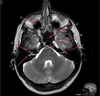

Image weighting and axis

T1 Sagittal

A

Lateral Ventricle

B

Corpus Callosum

C

Thalamus

D

Tentorium

E

4th Ventricle

F

Medulla Oblongata